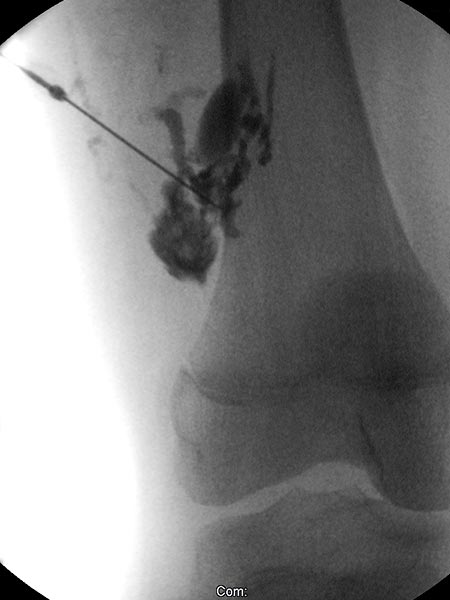

Digitale Subtraktionsangiographie nach Direktpunktion der venösen Malformation während der Sklerosierungsbehandlung. Neben der VM selbst zeigen sich direkte Kommunikationsvenen mit dem tiefen Leitvenensystem. Diese werden mittels Direktpunktion verschlossen mit viskösem Alkohol-Gel.

Röntgendurchleuchtung nach Direktpunktion der venösen Malformation während der Sklerosierungsbehandlung. Durch den Verschluss der Kommunikationsvenen mit dem tiefen Leitvenensystem ist die VM jetzt alleingestellt und kann sklerosiert werden. Nach Anspritzen kein Abstrom des Kontrastmittels mehr in die Leitvenen.